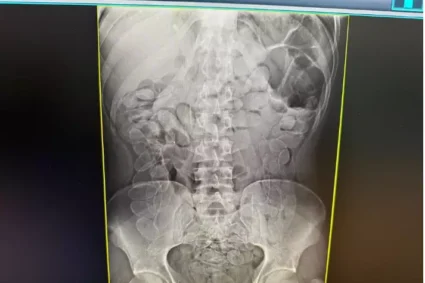

Mola exposta causou perfuração na coxa

No local, os militares encontraram a vítima consciente e orientada. A perfuração ocorreu no momento em que ela se sentou sobre o colchão, quando uma mola exposta atingiu a parte posterior da coxa direita.

Após avaliação técnica, foi constatado que o objeto metálico atingiu apenas a camada superficial da pele, sem provocar hemorragia significativa.